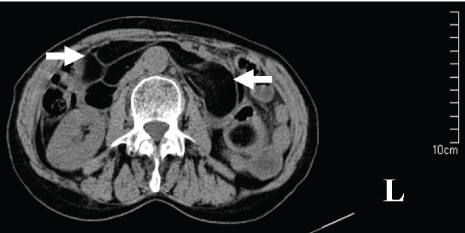

A 67-year-old woman was transferred to our hospital with one-day history of abdominal pain, vomit and constipation. She had a five years history of epigastric fullness and intermittent, upper abdominal pain in the past. CT revealed intestinal obstruction and hypodense lesions with CT value of -64 housefield units (HU) to -138 HU located from the descending part of the duodenum to the proximal jejunum, which was suggestive of lipomas [Table/Fig-1]. MR showed fat-containing mass lesions and the masses were high-intensity on T1-weighted and intermediately intensity on T2-weighted images [Table/Fig-2], with a drop in signal on T1 and T2-weighted fat-suppressed images [Table/Fig-3], consistent with a diagnosis of duodenal lipomas.

CT scan appearance of duodenal lipoma.

Because early symptoms are often nonspecific and vague, it is important to keep the diagnosis of DL in the differential diagnosis of obscure abdominal pain or gastrointestinal tract bleeding. Despite consideration of this diagnosis, it can still be difficult to confirm. Diagnosis can be established by radiological, endoscopic or operative means. Current imaging modalities, such as CT and MRI can provide an accurate diagnosis [16]. DLs appear on CT as a well-circumscribed hypodense lesion with a density ranging from -60 to -120 HU [59]. As fat suppression techniques effectively reduce the macroscopic fat signal, they are preferred in order to diagnose lipomas with MR [16]. Lipomas have high-intensity on T1-weighted images and usually present intermediate intensity on T2-weighted images. The loss of signal on fat-suppressed images enables the final diagnosis by MRI [16]. Though CT and MRI are helpful in diagnosis but these are unable to precisely locate the origin of the lesion. Direct visualization at endoscopy provides the clues about the nature of the tumour. In most cases, endoscopy has become the choice for diagnosis, either by the appearance of a pedunculate mass of fat or of a lesion stretching the sub-mucosa and when the mucosa is uncovered the shiny yellow colour of the lipoma becomes apparent “the naked fat sign” [44]. But it is generally insufficient in making a definitive diagnosis by endoscopy if the lipoma is submucosal or subserol. EUS is effective to provide information about the original layer, echogenicity, the depth and invasion [34]. The typical EUS findings for DLs are intense homogeneous hyperechoic mass originating from the submucosa, with echo attenuation behind and/or inside the rear area [58]. If the lipoma is within reach of the endoscope, a biopsy forcep can be used to prove the diagnosis. Before biopsy of the putative lipoma, however, the diagnosis might be suspected. The “naked fat sign”, “pillow sign” and “tenting sign” [17] have been said to be pathognomonic.